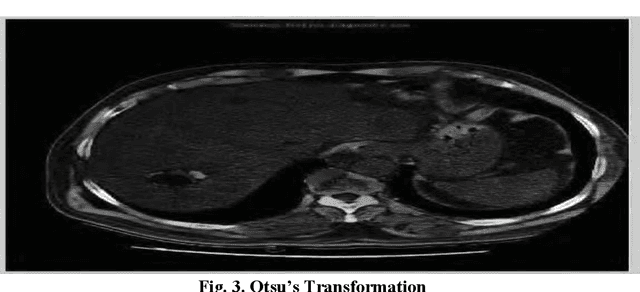

Abstract:Medical imaging is the most important tool for detecting complications in the inner body of medicine. Nowadays, with the development of image processing technology as well as changing the size of photos to higher resolution images in the field of digital medical imaging, there is an efficient and accurate system for segmenting this. Real-world images that for a variety of reasons have poor heterogeneity, noise and contrast are essential. Digital image segmentation in medicine is used for diagnostic and therapeutic analysis, which is very helpful for physicians. In this study, we aim at liver cancer photographs, which aim to more accurately detect the lesion or tumor of the liver because accurate and timely detection of the tumor is very important in the survival and life of the patient.The aim of this paper is to simplify the obnoxious study problems related to the study of MR images. The liver is the second organ most generic involved by metastatic disease being liver cancer one of the prominent causes of death worldwide. Without healthy liver a person cannot survive. It is life threatening disease which is very challenging perceptible for both medical and engineering technologists. Medical image processing is used as a non-invasive method to detect tumours. The chances of survival having liver Tumor highly depends on early detection of Tumor and then classification as cancerous and noncancerous tumours. Image processing techniques for automatic detection of brain are includes pre-processing and enhancement, image segmentation, classification and volume calculation, Poly techniques have been developed for the detection of liver Tumor and different liver toM oR detection algorithms and methodologies utilized for Tumor diagnosis. Novel methodology for the detection and diagnosis of liver Tumor.